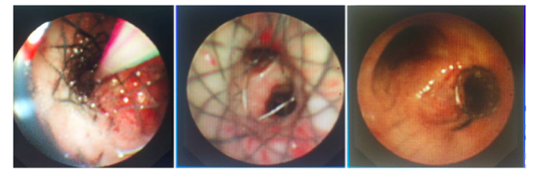

近日,我院腫瘤科收治了一名64歲危在旦夕的晚期肺癌患者,在腫瘤四區(qū)石琴主任、麻醉科柯敏副主任醫(yī)師和纖支鏡室連秀華護士長的協(xié)調(diào)配合下,用時僅3分鐘,成功植入支氣管金屬支架,極大改善患者生存質(zhì)量。

患者吳某某,一年前確診為早期左肺鱗癌,今年年初肺癌發(fā)展至晚期,化療4周期無效。6月初,患者癥狀明顯惡化,胸悶、憋氣、不能平臥,無法進行腫瘤放療。6月12日,經(jīng)我院石琴副主任醫(yī)師會診后考慮癌細胞轉(zhuǎn)移,巨大的淋巴結破潰至右主氣道,導致氣管外壓性狹窄,加之患者長期吸煙并慢性阻塞性肺疾病,肺儲備能力極低,故導致低氧血癥,平臥時喘憋感加劇。

左圖為術前支氣管                  右圖為巨大的淋巴結

住省腫瘤醫(yī)院7天該患者痛苦不堪,夜不能寐,精神狀態(tài)萎靡。家屬強烈要求我院石琴副主任醫(yī)師給病人實施右主支氣管金屬支架植入術。在評估手術風險和臨床獲益等各因素后,最后右主支氣管金屬支架植入術在我院麻醉科柯敏副主任醫(yī)師和纖支鏡室連秀華護士長協(xié)同配合下,石琴副主任醫(yī)師僅使用了3分鐘的時間給病人完成了右主支氣管金屬支架植入術。眼看著病人血氧飽和度從80%-86%-90%-99%。同時在給病人清除右下肺膿痰的2分鐘時間內(nèi),病人居然就昏昏入睡了。

術畢,當醫(yī)護人員喚醒患者時,患者含淚說道:“我剛才居然就睡著了,真的好舒服呀!”全手術室醫(yī)護人員深深的松了口氣,同時每個人臉上都充滿了成功的喜悅。真心希望我們治療過的患者都能發(fā)出如此舒心的微笑,您們的笑容就是我們的成就感,再忙再累我們醫(yī)務人員都在所不辭!

對于我院來說,氣管支架植入術并非首例,但是病人危在旦夕又行該手術的確屬首例。看到病人和家屬舒心微笑,顛覆了我們既往的治療理念,對于部分晚期肺癌患者局部治療仍然是一種行之有效的手段,不但提高了患者的生活質(zhì)量,同時更為下一步的治療策略爭取更多的時間和空間。